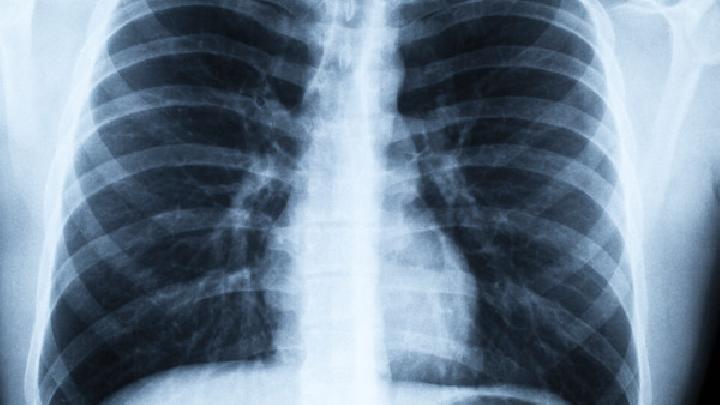

首先要治疗各种慢性呼吸道疾病。

肺性脑病治疗前的注意事项

2.控制呼吸道感染,合理使用抗生素(青霉素、先锋霉素、利复星等)。

3.改善呼吸功能、缺氧和二氧化碳潴留。

4.纠正酸碱平衡障碍。

5.对症治疗神经和精神障碍。